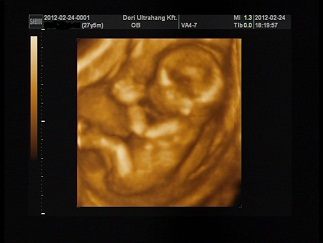

Igigig! Nagyon jó lett a sztárfotó! Gratula!